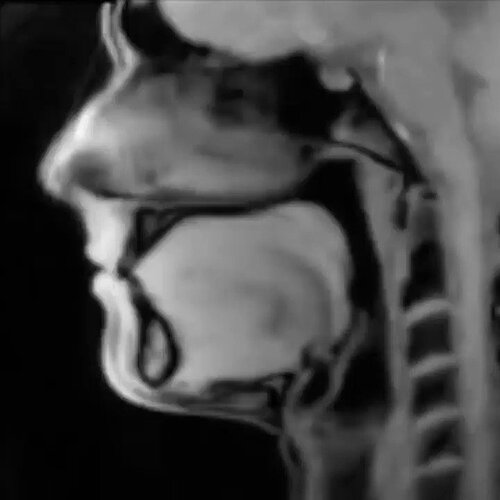

An MRI of the mechanics of speech

An MRI of the mechanics of speech.